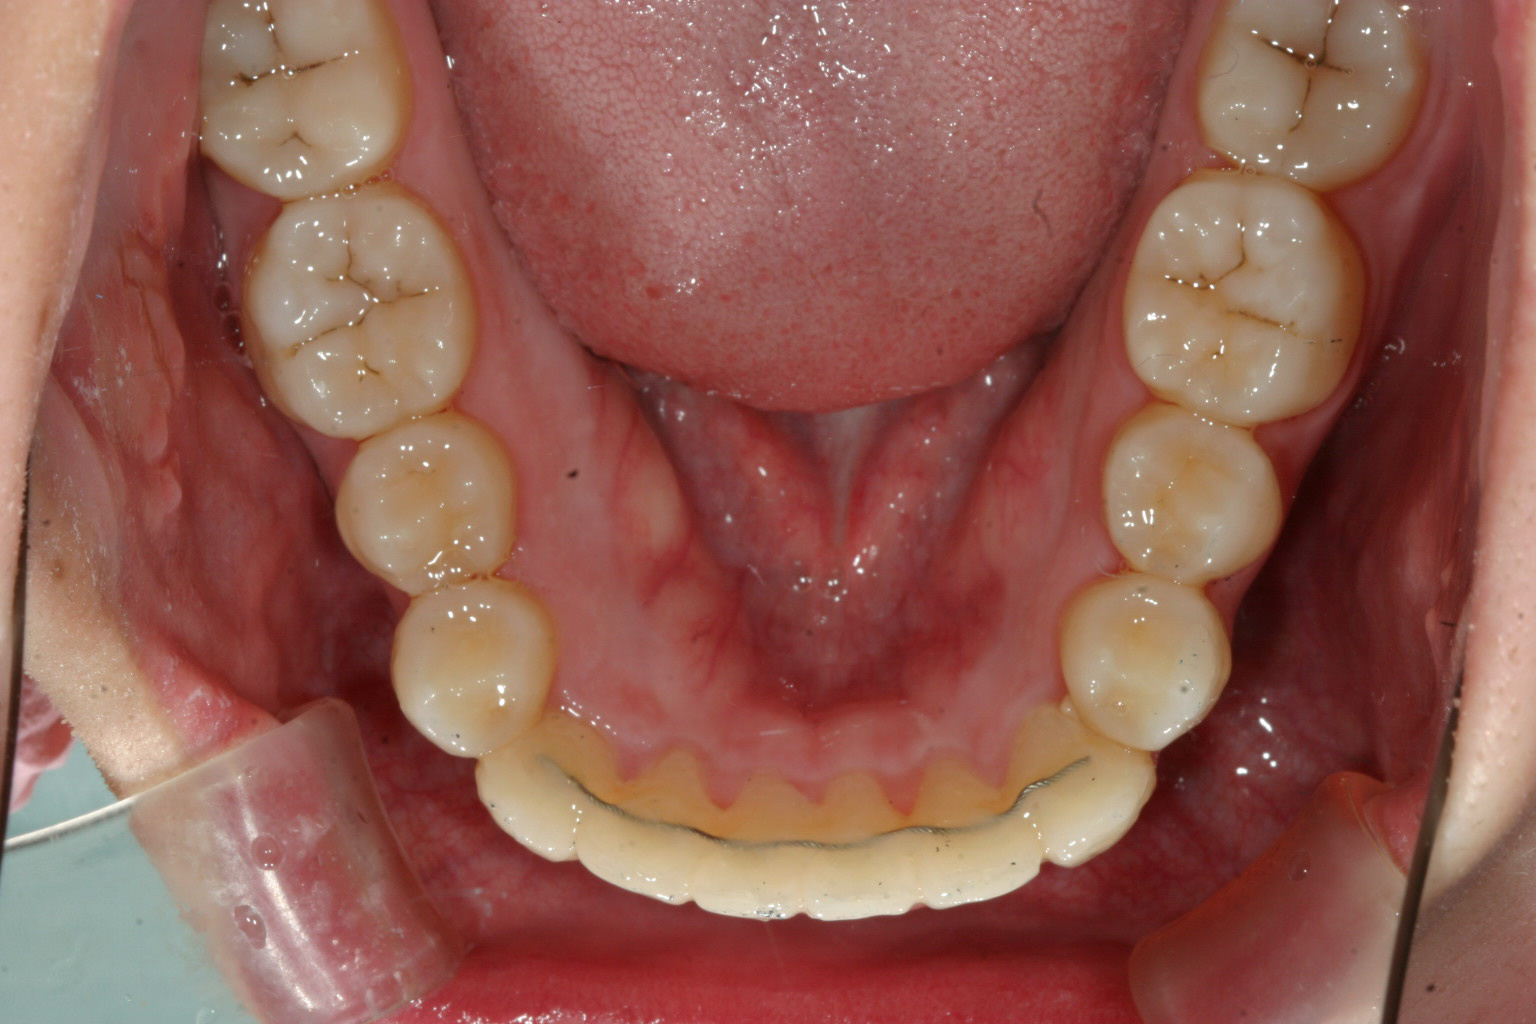

下顎はV字が特にひどく小臼歯あたりが狭くなっています。

下顎も綺麗に修正出来ました。

今回の症例は稀にみる下顎のアーチフォームの乱れが激しく乱れていましたのでこれを修正するのに手間取りました。

多少下顎のアーチフォーム改善にワイヤーを使用しましたが、これだけ綺麗になれば患者様にも満足して頂けました。